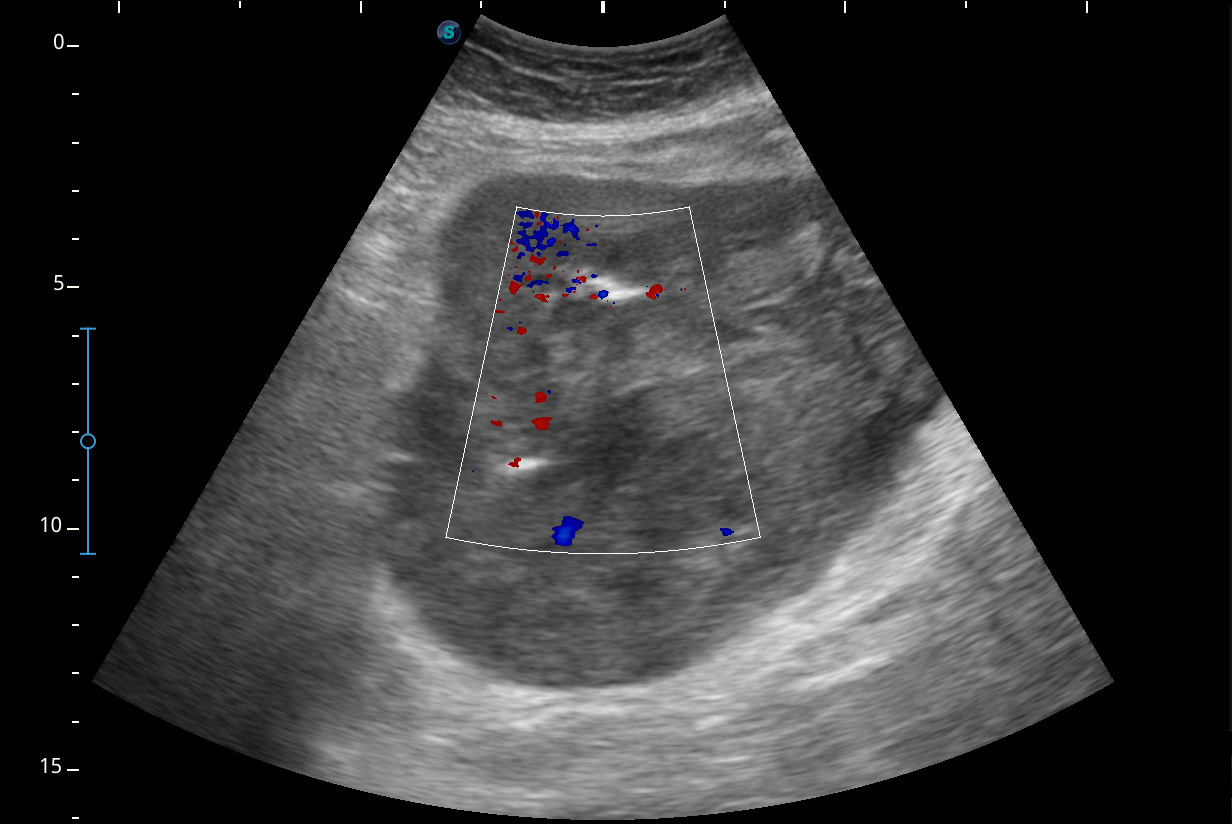

Hallazgos ecográficos

Se visualiza una masa heterogénea de unos 10 x 13 cm aproximadamente de diámetro con posibles focos necróticos y captación Doppler color, de dudosa organodependencia, que podría corresponder a un sarcoma retroperitoneal.